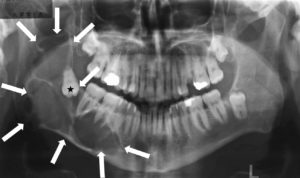

Οδοντοφατνιακή Χειρουργική – Έγκλειστα δόντια